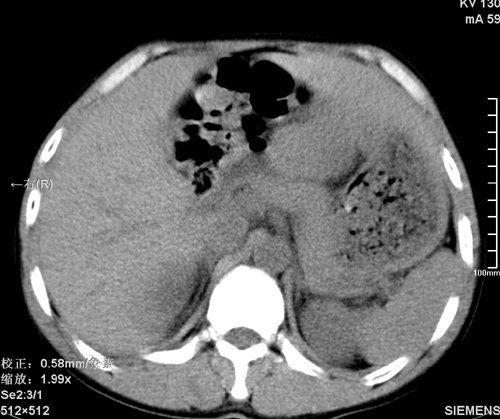

以下是引用tao772在2008-3-28 12:29:00的发言:[br]右侧腹膜后积血,右侧腰大肌挫伤,右侧部分横突骨折. 肾脏最好报一下挫伤,必要时增强。